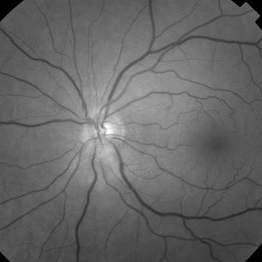

Red Free - Astrocytic Hamartoma

66-year-old white male without history of tuberous sclerosis was found to have an incidental, asymptomatic, translucent, retinal lesion with a few small telangiectatic vessels within it. The FA showed early hyperFL of these small vessels with prominent late leakage/staining. The OCT showed a retinal mass with a "moth eaten" appearance. Vision was 20/20 and the rest of the exam was unremarkable.